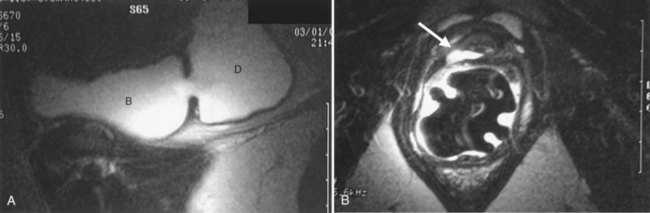

As an alternative to PPU, VCUG may provide excellent imaging of UD (Fig. 78–20). It is widely available and is a familiar diagnostic technique to most radiologists. Sensitivity for UD with this technique varies from 44% to 95% (Ganabathi et al, 1994; Jacoby and Rowbotham, 1999). Patients often will have difficulty in initiating micturition in the radiology suite due to the pain associated with urethral catheterization, psychogenic inhibition due to voiding in the presence of others, or other factors. In the absence of voiding, the urethral diverticulum will not be seen. Therefore a VCUG which does not demonstrate a urethral diverticulum but did not contain voiding images or postvoid images is nondiagnostic. If the patient is unable to void under fluoroscopy during the VCUG, an attempt should be made to void in the privacy of an adjacent bathroom. If voiding in private was successful, a postvoid film taken under these circumstances will likely show a collection of contrast inferior to the bladder demonstrating the urethral diverticulum. Unfortunately, an inability to generate an adequate flow rate during the VCUG will result in suboptimal filling of the UD and an underestimation of its size and complexity (Fig. 78–21). Three-dimensional CT VCUG with reconstructions is being investigated as a novel imaging technique for UD but is not yet widely available clinically (Kim et al, 2005).

Figure 78–21 Voiding cystourethrogram (VCUG) and MRI from a patient with a large circumferential urethral diverticulum (UD). The voiding image from the VCUG (A) shows poor opacification of the proximal urethra with suboptimal distention of the UD due to a poor voiding effort. The endoluminal MRI demonstrates the full extent and complexity of the lesion on the T2 axial (B), midline sagittal (C), and parasagittal (D) images.